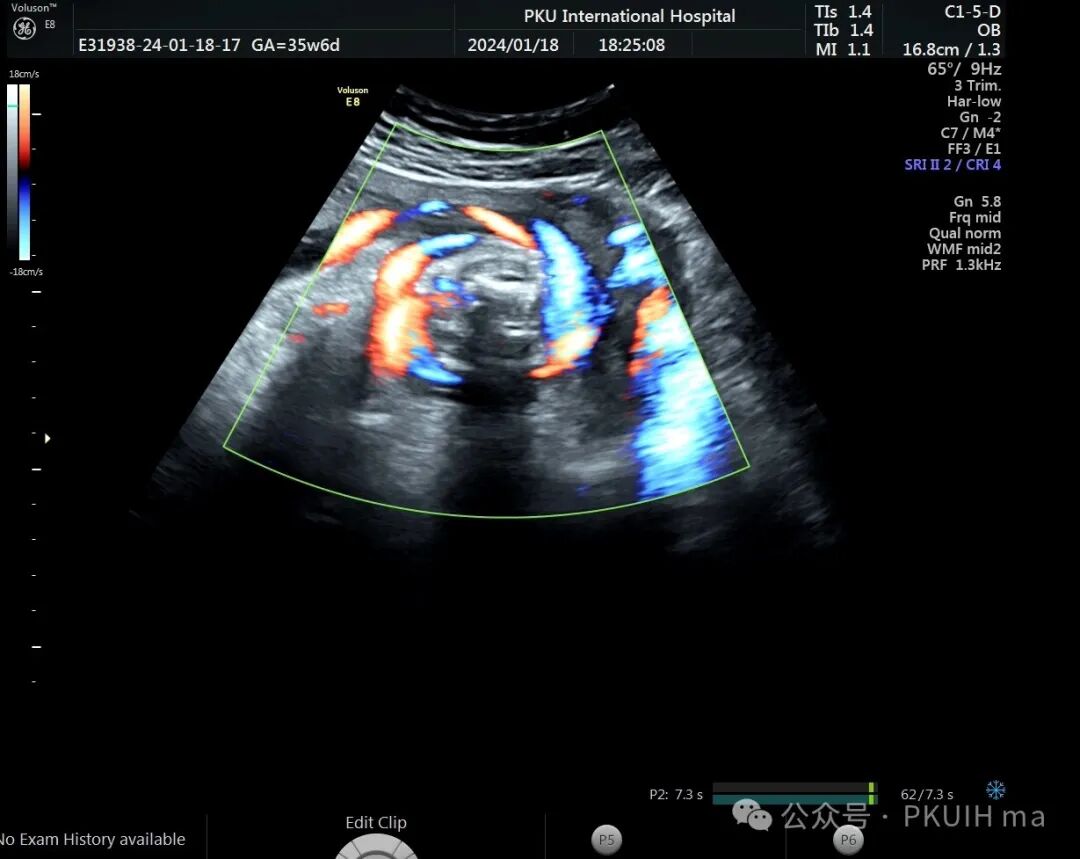

前两天碰到一孕妇胎动减少来诊,孕妇自述下午两点开始发现胎儿无明显胎动,吃了甜的食物和改变姿势还是不怎么动,随于下午六点左右来诊。超声发现胎儿绕颈两周以上且绕的较紧,检查中发现胎儿心率快,胎儿无明显胎动,绕颈处脐动脉血流加速时间延长,胎儿大脑中动脉阻力低,反复测量两侧大脑中动脉阻力均低。胎心监护也不好,随后产科采取紧急剖宫产。

反复测量左右两侧大脑中动脉阻力均低于第五百分位,考虑胎儿存在缺氧